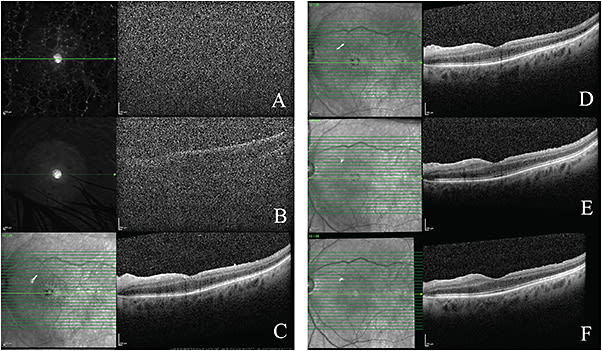

On his postoperative day (POD) 1 visit, the patient had counting fingers (CF) vision OS and normal intraocular pressure (IOP). There was a limited view of the fundus that affected the quality of optical coherence tomography (OCT) (Figure 1A), and B-scan ultrasonography demonstrated mild vitreous opacities without evidence of retinal detachments or masses. Anterior segment examination of the left eye was notable for 1+ corneal edema, an IOL in good position, and a green hue in the vitreous cavity, consistent with retained ICG. The anterior segment and fundus exam of the right eye were normal. Given the known risk of toxicity to the RPE, a pars plana vitrectomy (PPV) was recommended for the next day.

The patient returned on POD 7. He continued to have HM vision but now had worsening corneal edema and an elevated IOP of 44 mmHg. His topical prednisolone acetate was increased to 6 times per day, and he was started on dorzolamide/timolol twice daily and brimonidine 3 times daily. Four days later, on POD 11, his vision improved to 20/400 and IOP to 15 mmHg. His corneal edema resolved and a view to the fundus improved but still limited a good quality OCT (Figure 1B).

On POD 28, the patient’s blurred vision was improving. His best-corrected visual acuity (BCVA) was 20/100, and his IOP was within normal limits. There was no relative afferent pupillary defect (RAPD) noted, and the confrontation visual field demonstrated a persistent severe central blur. OCT of the left eye showed retinal thinning with outer retinal layer disruption, particularly in the temporal macula (Figure 1C). The fundus exam showed resolving ILM staining from the ICG, consistent with the fundus photography done that day (Figure 2). At this point, the patient was instructed to continue topical prednisolone acetate 4 times daily and brimonidine 3 times daily.

At subsequent follow-up visits, the OCTs (Figure 1, D-E) showed progressive improvement in the outer retinal layer integrity. During the patient’s most recent follow-up, postoperative day 100, IOP was normal without any topical drops, and BCVA remained 20/100 (Figure 1F).